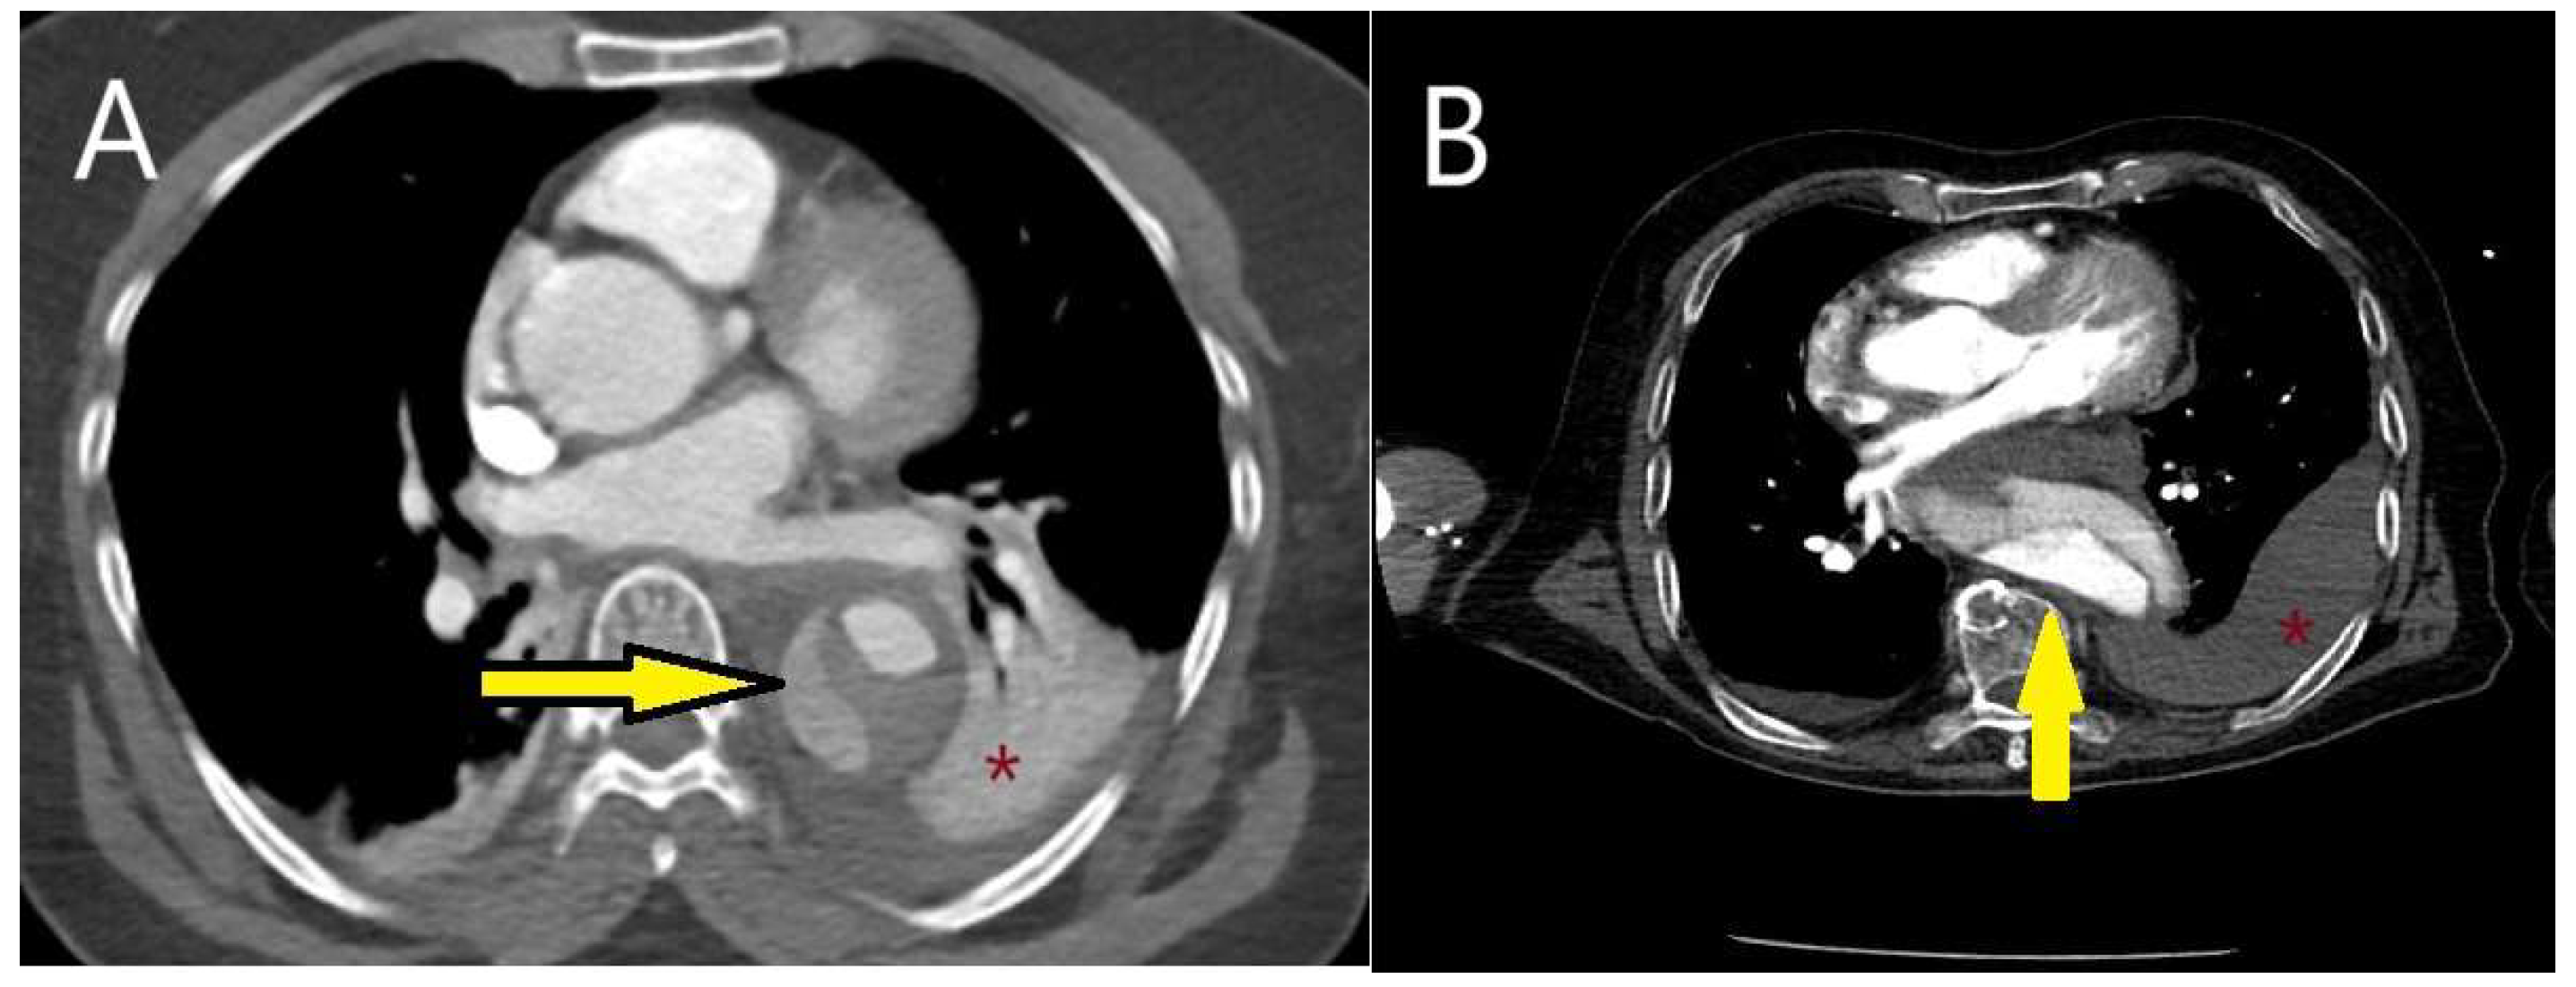

5.2.3. Computed Tomography

- Sathiadoss, P.; Haroon, M.; Wongwaisayawan, S.; Krishna, S.; Sheikh, A.M. Multidetector Computed Tomography in Traumatic and Nontraumatic Aortic Emergencies: Emphasis on Acute Aortic Syndromes. Can. Assoc. Radiol. J. 2020, 71, 322–334. [Google Scholar] [CrossRef] [PubMed]

- Ko, J.P.; Goldstein, J.M.; Latson, L.A., Jr.; Azour, L.; Gozansky, E.K.; Moore, W.; Patel, S.; Hutchinson, B. Chest CT angiography for acute aortic pathologic conditions: Pearls and pitfalls. Radiographics 2021, 41, 399–424. [Google Scholar] [CrossRef] [PubMed]

- Dreisbach, J.G.; Rodrigues, J.C.L.; Roditi, G. Emergency CT misdiagnosis in acute aortic syndrome. Br. J. Radiol. 2021, 94, 20201294. [Google Scholar] [CrossRef]